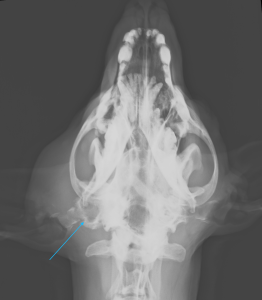

こんにちは、獣医師の依田です。 今回は、耳の根元の腫れで来院したわんちゃんの紹介です。 飼い主様が数日前から耳…]]>

こんにちは、獣医師の依田です。 今回は、耳の根元の腫れで来院したわんちゃんの紹介です。 飼い主様が数日前から耳…]]>